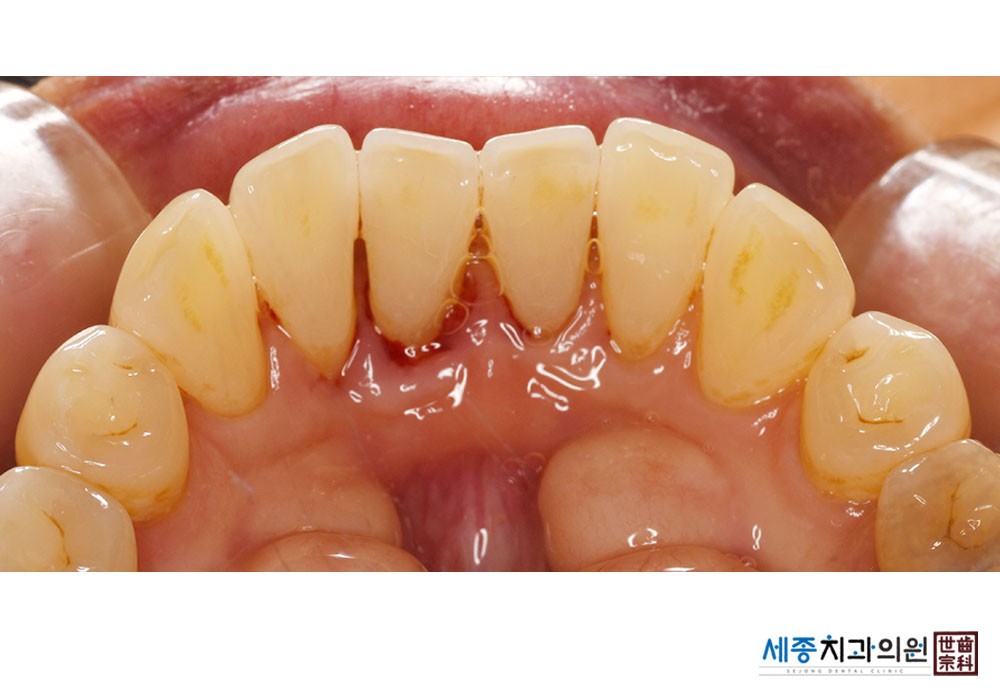

[스케일링] 치주질환 예방 스케일링

치료전 : 2023-11-15

치료후 : 2023-11-15

가글마취&저주파 스켈러를 사용한 착색제거 스케일링